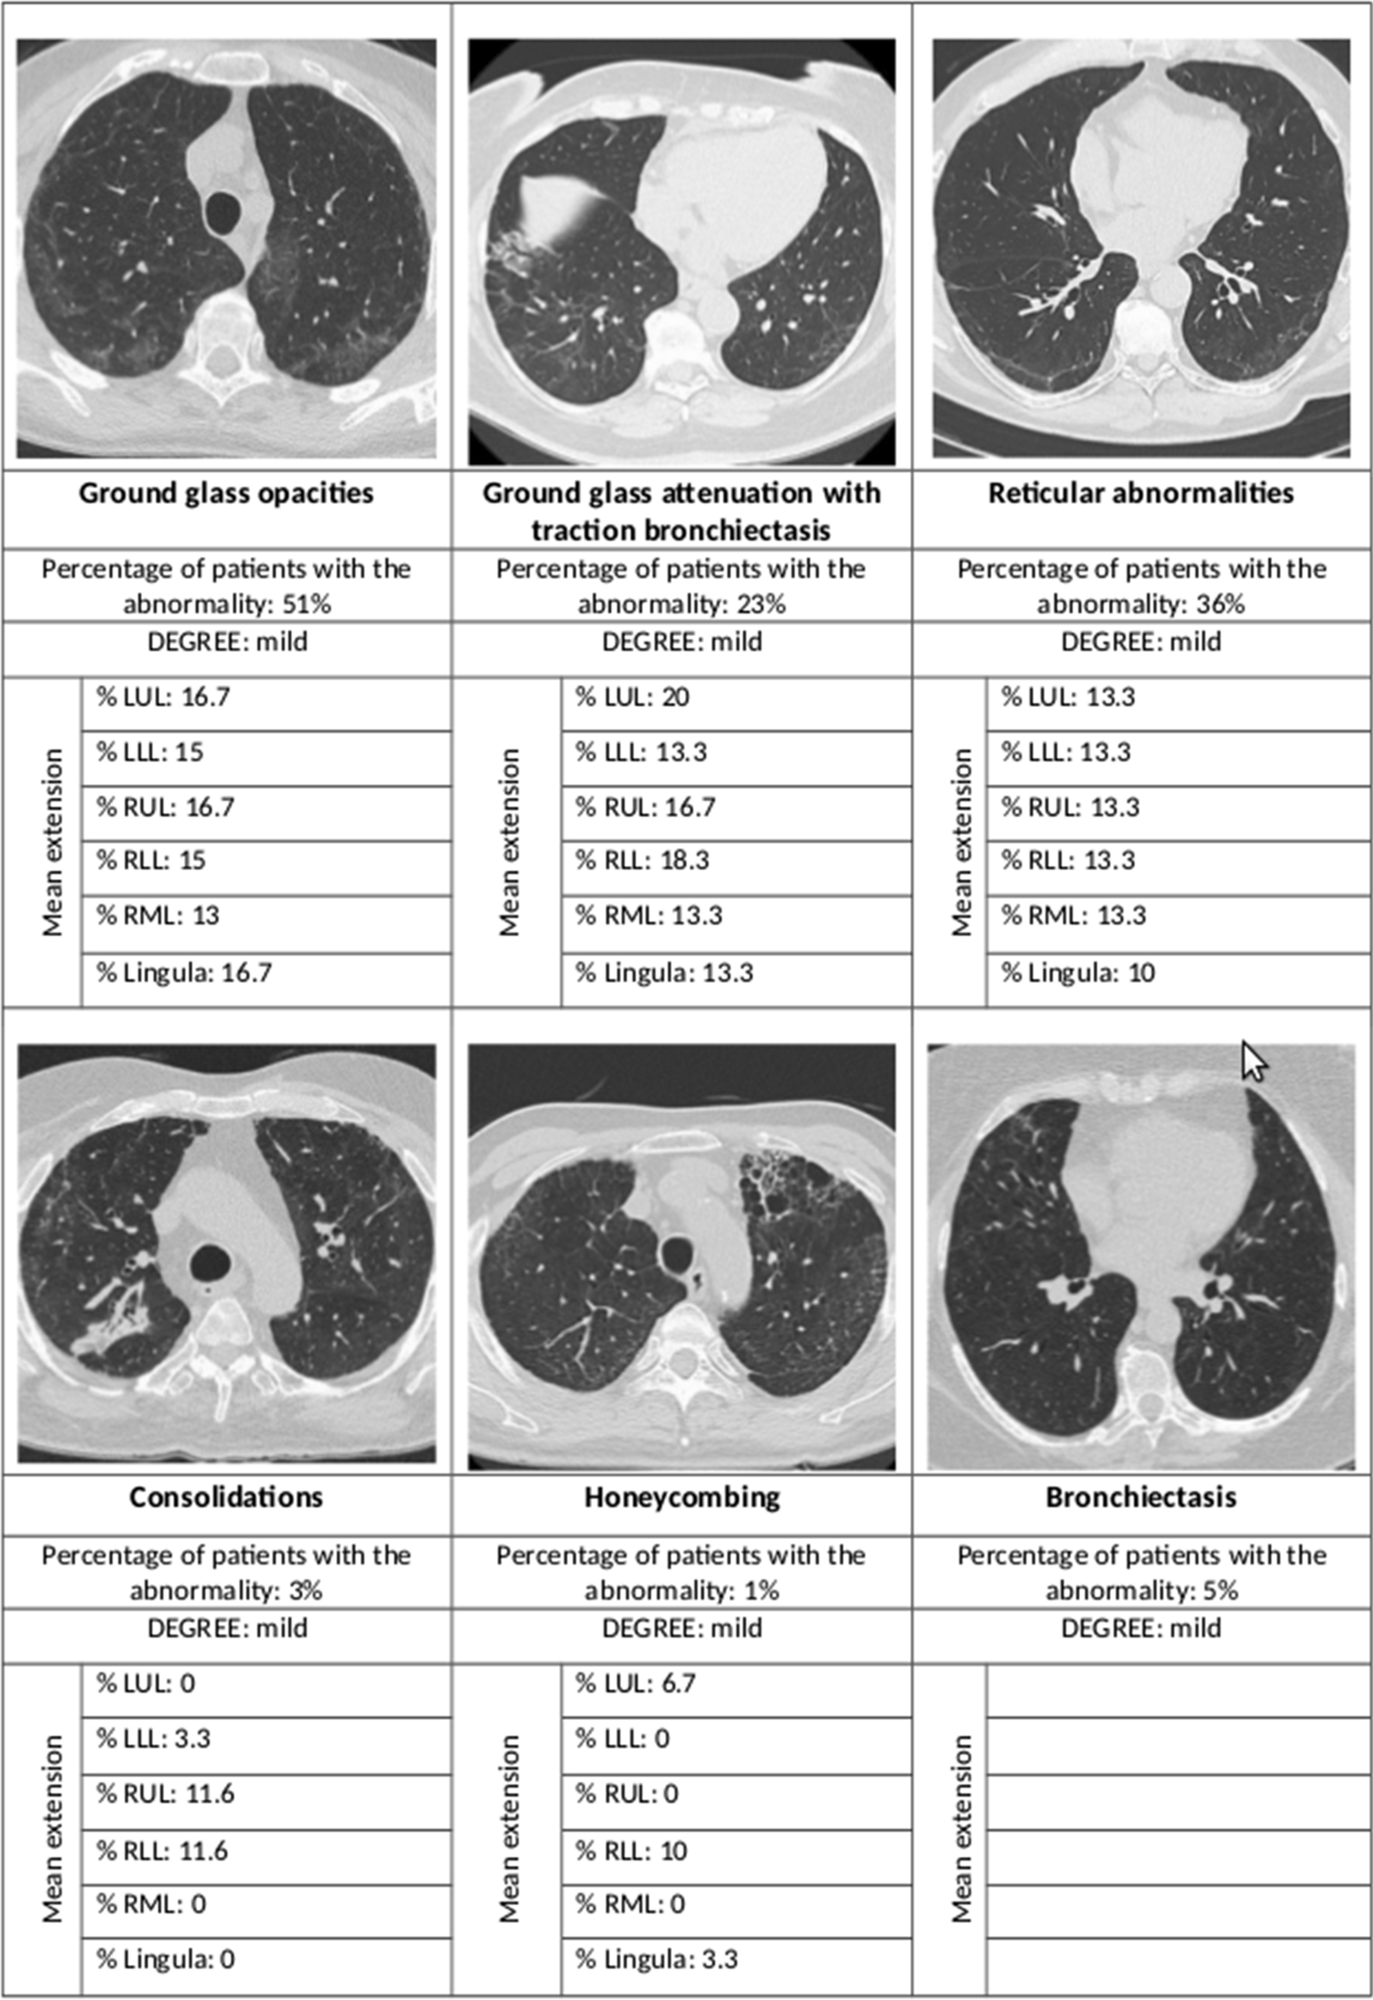

Summary of the main radiological abnormalities and their extension according to the lung lobe involved. LUL left upper lobe, LLL left lower lobe, RUL right upper lobe, RLL right lower lobe, RML right middle lobe

Radiological abnormalities were seen in 80% of the IMV patients, 65% of the CPAP, and 46% of the oxygen-only group. The risk was more than eight times higher in the first group and almost three times in the second group, compared to the last.

Most of the high-resolution CT (HRCT) scans showed interstitial lung changes; over half showed ground-glass opacities, over a third had reticular abnormalities, while less than 5% each showed consolidations and honeycombing. In 44% the ground glass opacities were accompanied by traction bronchiectasis or bronchiectasis.

The findings show that fibrosis of the lung is an uncommon finding after SARS-CoV-2 pneumonia requiring hospitalization, with only 1% of patients showing this complication at 12 months from discharge. Most cases showed other mild interstitial results, mostly ground-glass opacities and reticular abnormalities, mainly within a single lobe and limited in extent.